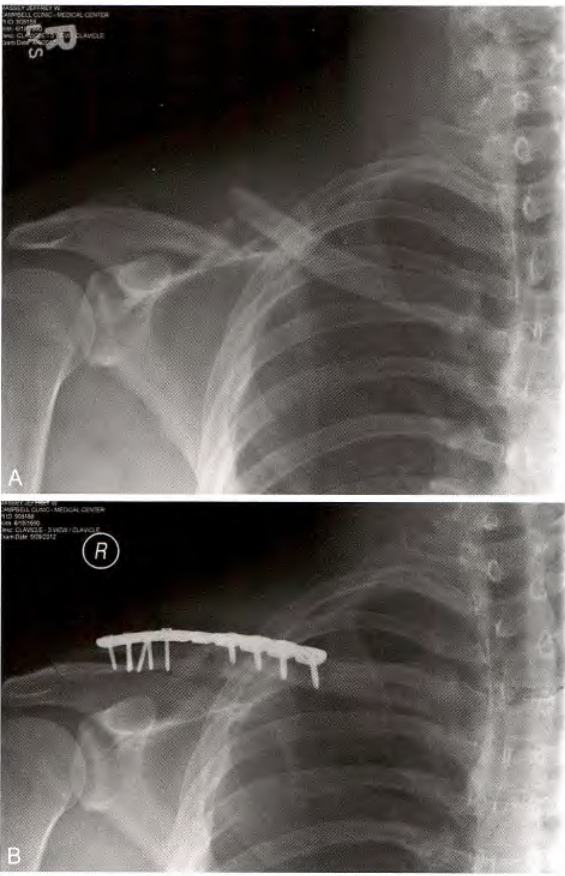

一. 钢板内固定

钢板和螺钉固定

A.锁骨骨折, B.前方钢板固定

锁骨骨折的切开复位内固定

前下方钢板和螺钉固定